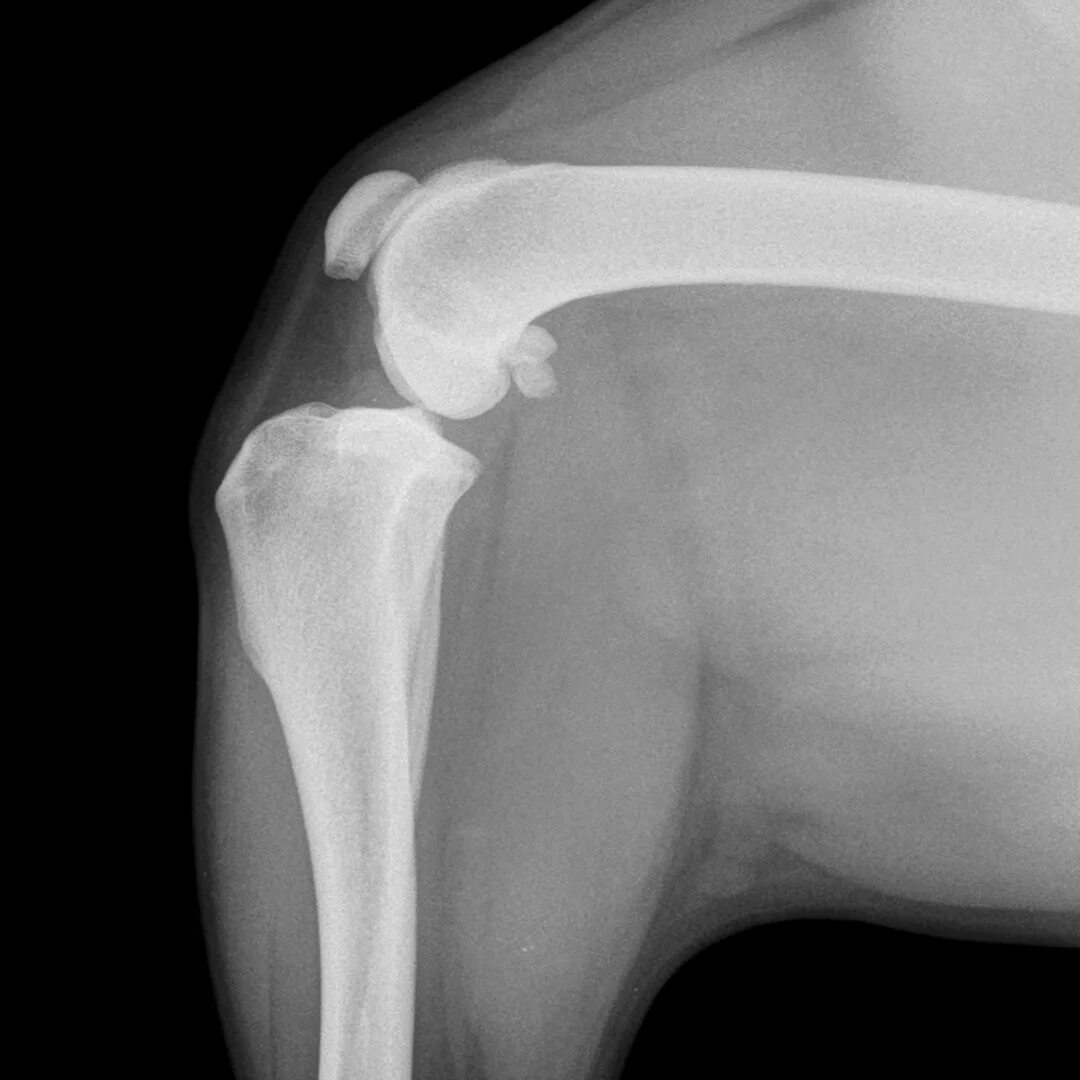

Операция суставов собак